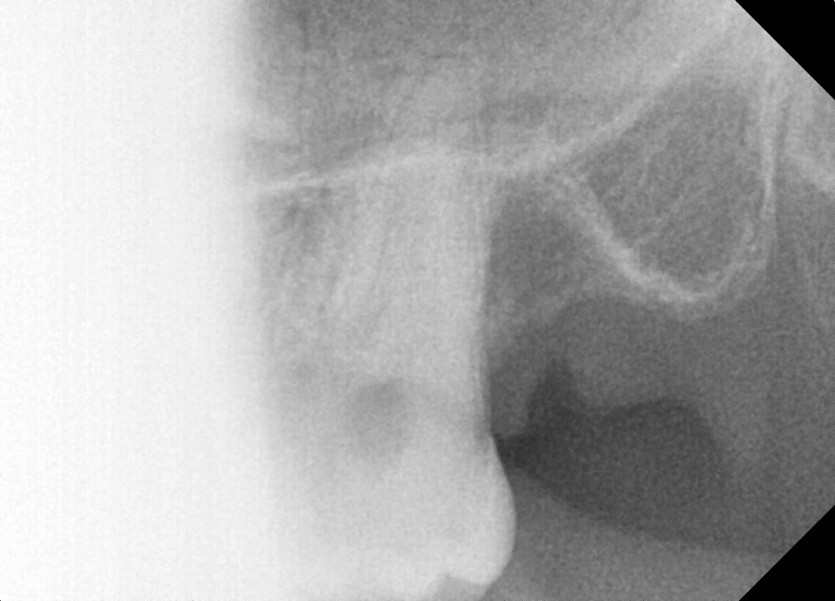

#28,38 사랑니 발치

구강 외과 전문의가 당일 발치했습니다.